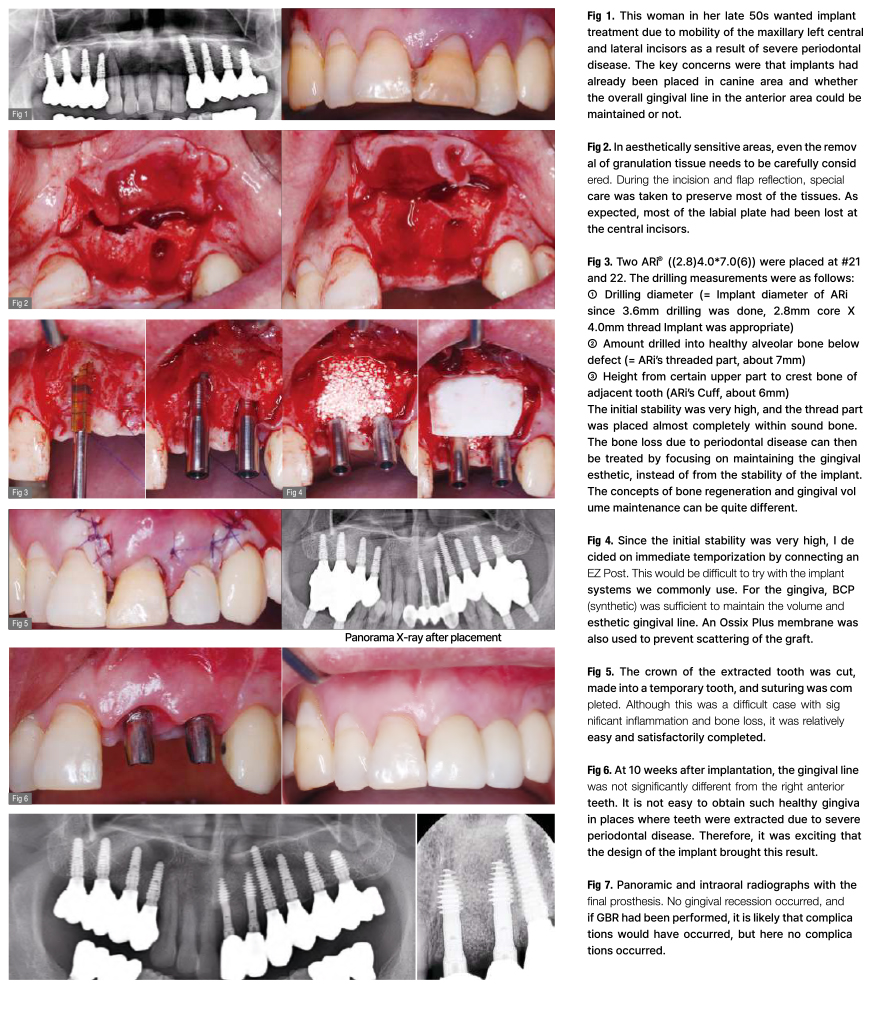

Como tratar estes casos?

É possível colocar implantes numa crista anterior atrófica e fina?

Caso muito grave de periodontite, com defeito ósseo extenso, sem cortical labial e perda óssea vertical. Será possível colocar implantes?